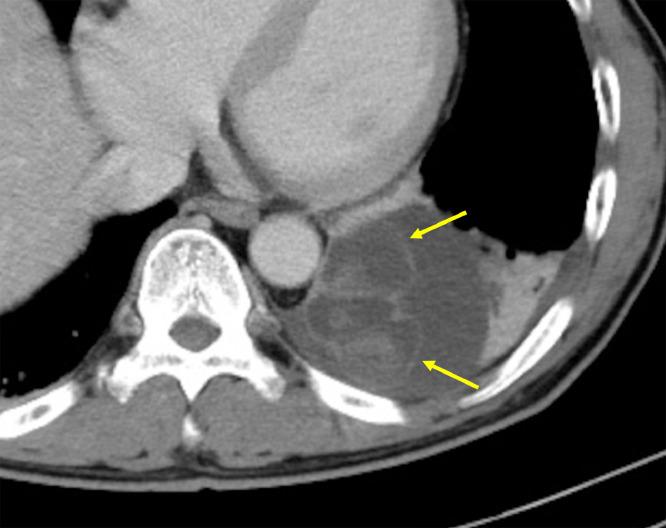

Bronchogenic cysts are the most common primary cysts of the mediastinum. Although most are asymptomatic, some bronchogenic cysts cause symptoms such as chest pain and dyspnea. Here, we report a case of bronchogenic cyst that ruptured twice in a short period of time in a patient who presented with sudden back pain. The lesion was apparent on computed tomography (CT) as a mass lesion with heterogeneous and high attenuation in the posterior mediastinal region. CT-guided puncture performed for diagnostic purposes revealed the contents as bloody fluid. The patient suffered chest pain approximately 3 months after the first presentation, and re-growth and re-rupture of the mass was suspected. The lesion was surgically resected and pathologically diagnosed as a bronchogenic cyst. Spontaneous rupture is a very rare complication of bronchogenic cyst, usually into the trachea, pleural cavity, or pericardial cavity. However, there are no reports of multiple ruptures. This case highlights the importance of recognizing the atypical imaging findings of bronchogenic cyst and the rare complication of rupture.

支气管源性囊肿是纵隔最常见的原发性囊肿。虽然大多数无症状,但一些支气管源性囊肿会引起胸痛和呼吸困难等症状。在此,我们报告一例支气管源性囊肿在一名突发背痛的患者中短期内破裂两次的病例。在计算机断层扫描(CT)上,病变表现为后纵隔区域的一个具有不均匀高衰减的肿块。为诊断目的进行的CT引导下穿刺显示内容物为血性液体。患者在首次就诊约3个月后出现胸痛,怀疑肿块再次生长并破裂。病变经手术切除,病理诊断为支气管源性囊肿。自发性破裂是支气管源性囊肿非常罕见的并发症,通常破裂入气管、胸腔或心包腔。然而,尚无多次破裂的报道。该病例凸显了认识支气管源性囊肿非典型影像学表现及罕见破裂并发症的重要性。